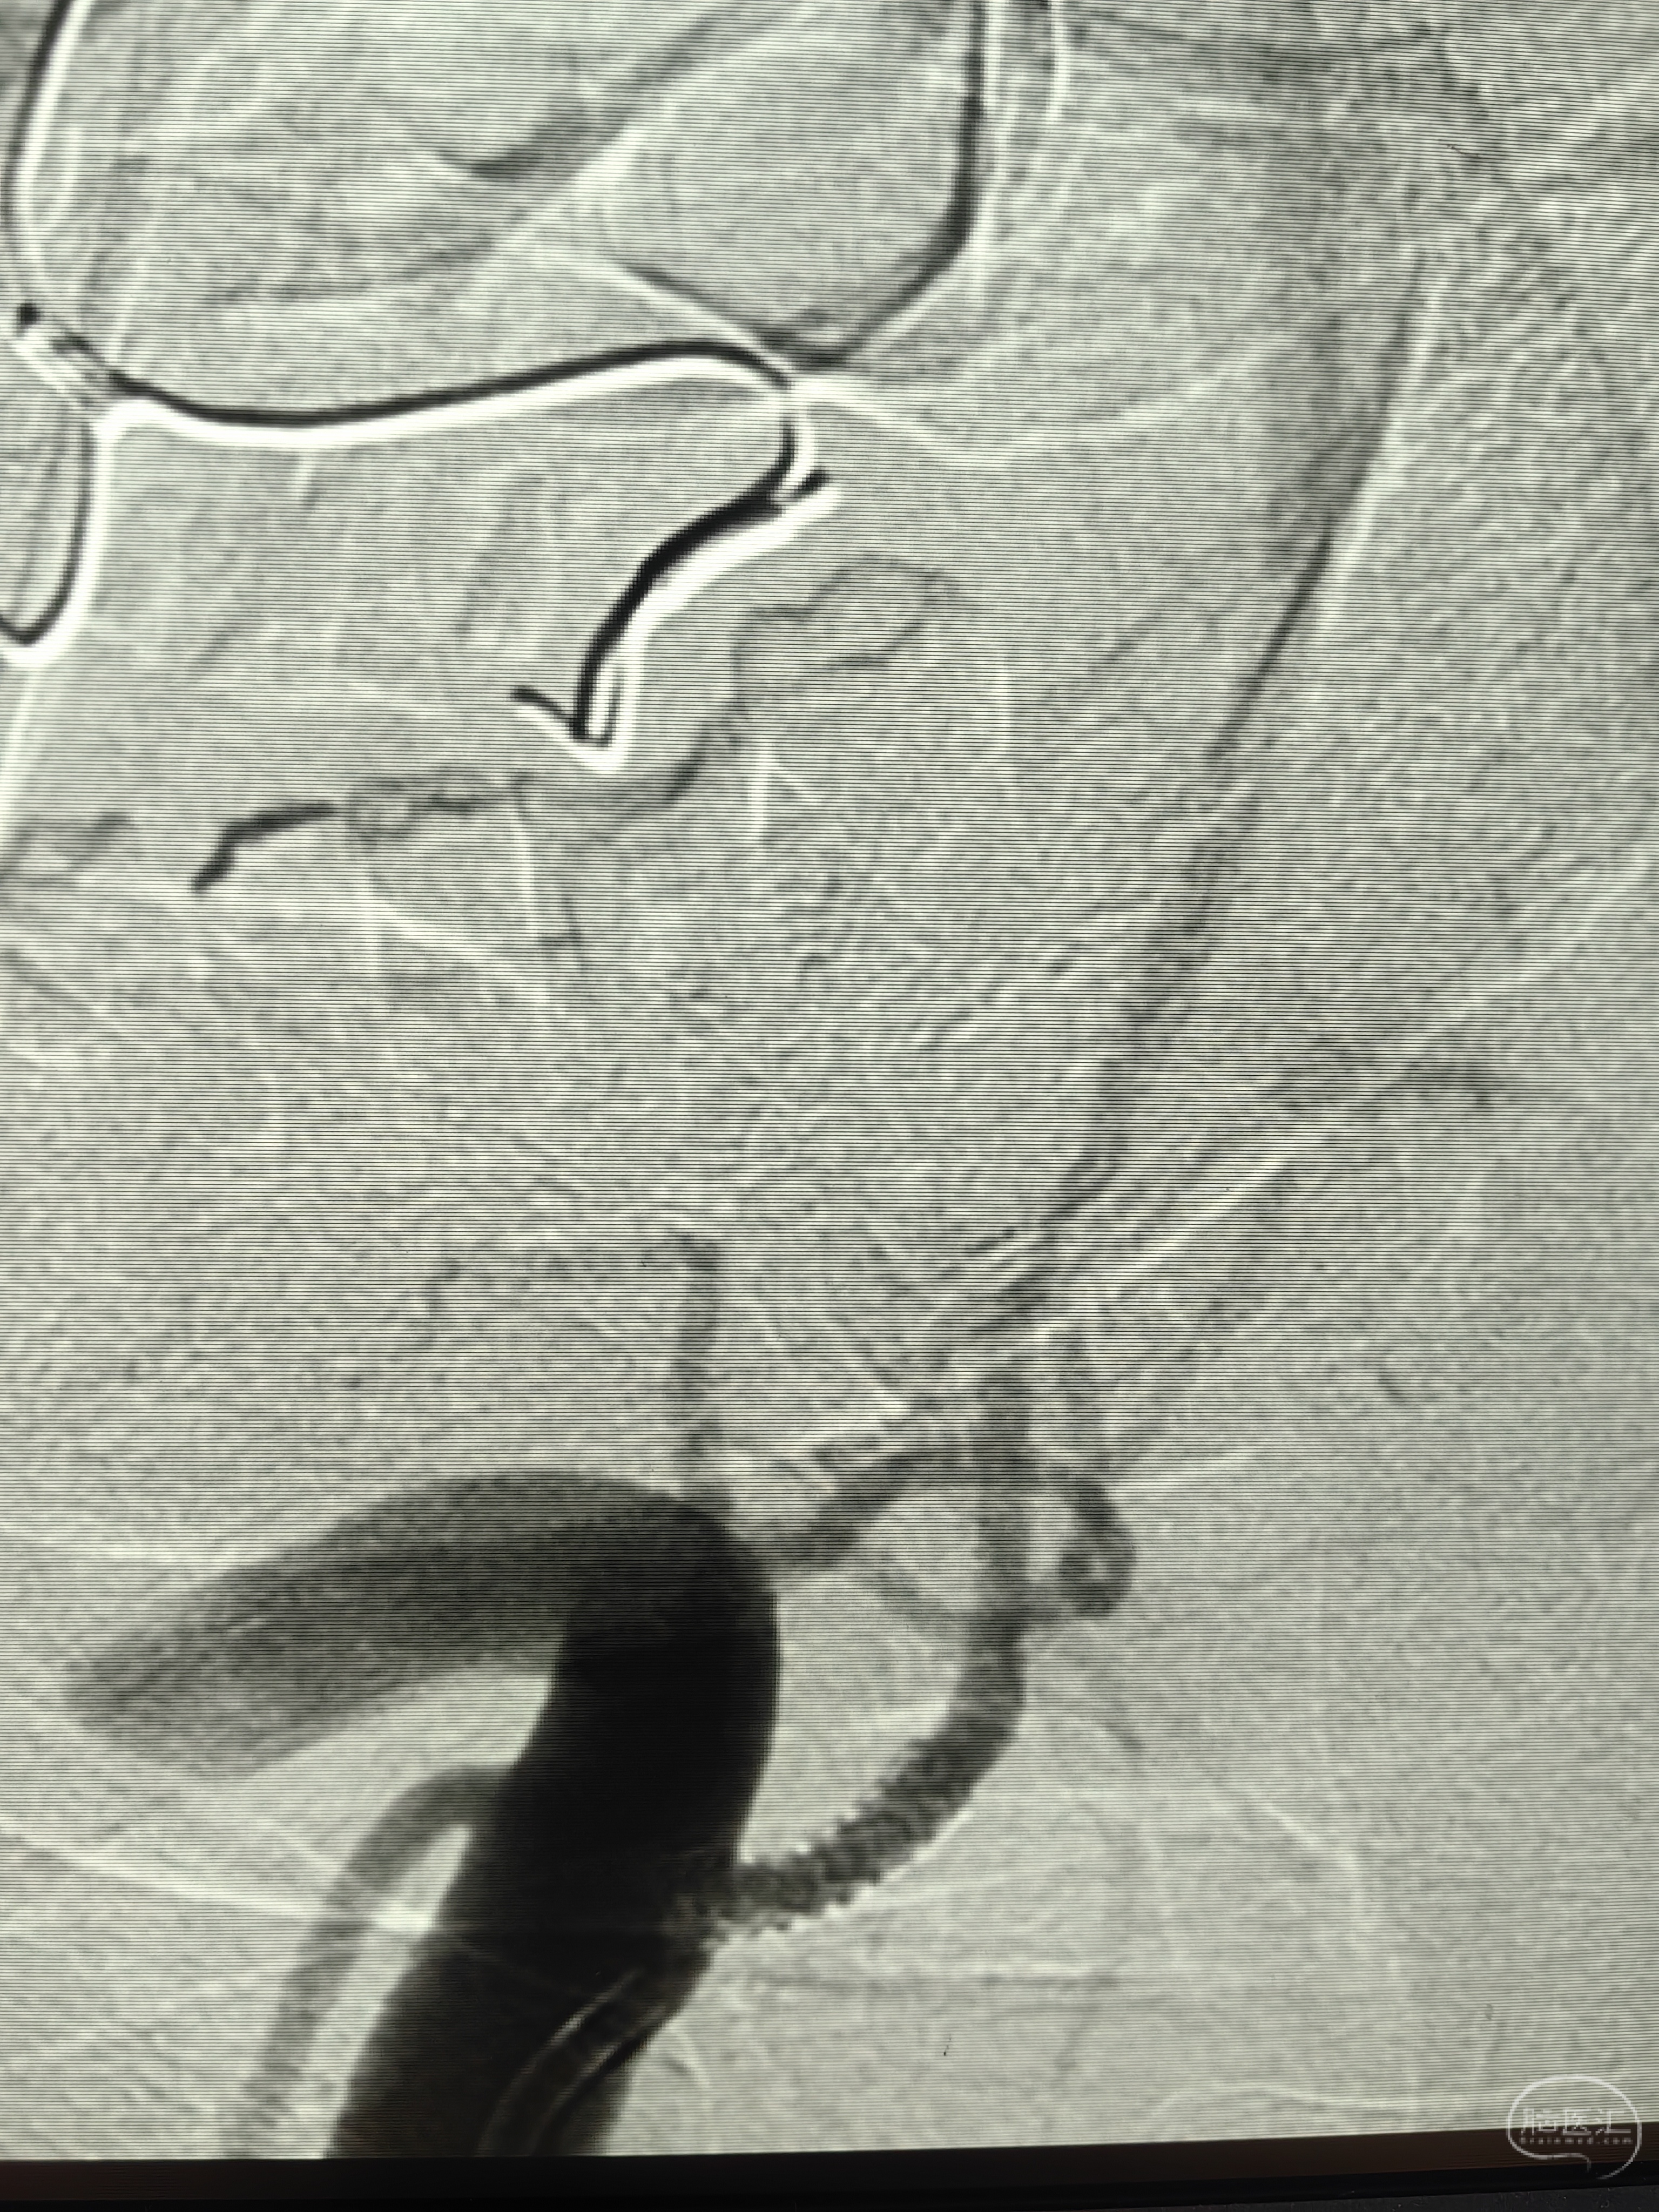

下夜班,手术完成后回家,捧起手机简单汇报一下:中老年女性,后循环小梗死,左侧椎动脉闭塞未见残端,右椎开口次全闭塞。本次计划治疗右椎开口。

路径:右椎开口,直接上JR3.5,放大造影:

JR提供的朝向其实也不够好,看看每次走微导丝的样子